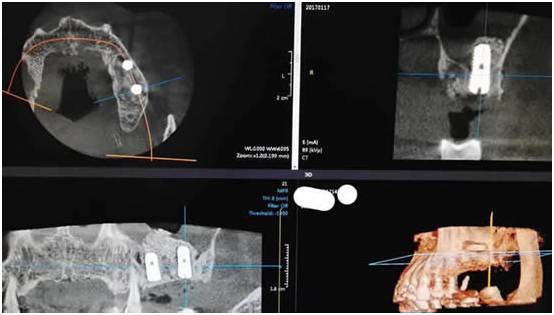

图五:术后CT(植入的骨粉以每个月一个毫米的速度变成自己的骨头,半年后他就可以有可以媲美真牙的种植牙了,就可以吃香喝辣了)

图六:术后CT

3、手术30分钟完成,种植体是韩国奥齿泰,直径5.0毫米,长度是11.5毫米。